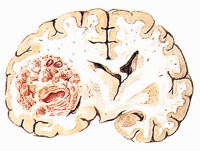

(1)結節型:這是最常見的類型,病變大小差異很大,大者直徑可達10cm以上小者常常肉眼無法看見又可分為單發和多發,多發者常常是由於瘤細胞分次或經不同的動脈系統同時進入腦內所致。腫瘤常呈球形,邊界清楚,初始在白質與皮質交界處生長後逐漸長大,內向白質生長,外可侵及硬膜,生長速度常較快,若伴有出血或囊性變可急劇起病,臨床症狀明顯腫瘤質地軟硬不等,血運不豐富,可呈紫色,也可為灰黃色或灰紅色,腫瘤較小時常呈實體性若長大且生長快常有中心部分囊性變甚至出血,囊腔內含有黃色淡紅色或咖啡色液體,個別呈膿性,腫瘤周邊水腫明顯致使邊界相對清楚,其水腫程度可與腫瘤種類、腫瘤血管的數量和通透性、局部代謝及腫瘤細胞分泌的液體有關,也可與腫瘤的轉移機制動脈血供的特殊性以及大腦上靜脈解剖上的特殊性有關但水腫與腫瘤的惡性程度沒有明顯關係。顯微鏡下腫瘤組織之間邊界不清,瘤細胞巢常沿血管外膜及腦組織向四周浸潤,周圍組織水腫、軟化及膠質增生。其組織特點與原發瘤的特點相一致,明顯者可由此而推斷出原發瘤,以指導臨床尋找原發灶加以治療。但在分化程度較低者並不能明確原發病灶,常與臨床上的膠質瘤特點相混,若出現腺瘤樣或乳頭狀結構可能誤診為室管膜瘤。但轉移瘤有其本身固有的特點如癌細胞常單個散在於正常神經細胞、炎症灶或凝固性壞死背景中,邊界清,核增大有異型性核漿比值增加,核膜明顯核仁變大,染色質呈網狀,胞質內還可出現空泡等。

腫瘤外觀1.腦原發性腫瘤 根據病史,特別是晚期全身癌腫患者出現顱內占位時,一般不難鑑別,必要時可作CT等檢查。良性腦原發性腫瘤有其自身特點,易於鑑別。惡性腦膠質細胞瘤,有時難與本病鑑別,需藉助活檢。表淺的腦膜轉移瘤須與小的腦膜瘤鑑別,後者往往沒有明顯症狀和瘤周腦水腫。有顱骨破壞者,尚需與腦膜瘤或顱外病變引起的顱骨改變相鑑別但是某些腦原發性腫瘤少見情況下可伴有腦轉移瘤,此時明確鑑別是不可能的。文獻報導的原發性腦瘤多為良性如腦膜瘤、聽神經瘤、垂體瘤等,偶為星形細胞瘤。腦轉移瘤多見於乳腺癌和肺癌這與腦轉移瘤的一般規律符合,乳腺癌和肺癌為女性和男性常見的腫瘤,均傾向中樞神經系統轉移。這種瘤的轉移機制沒有明確的解釋,可能因為良性腦瘤好發年齡與腦轉移瘤相近,良性腦瘤存活期較長和有較豐富血供及嬌嫩的腫瘤間質,這些為轉移瘤提供了有利條件。

腦內變化1.治療原則